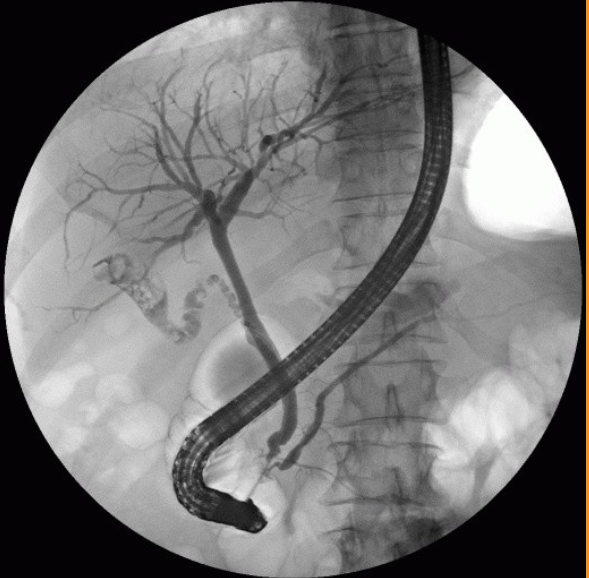

What contrast procedure was performed to produce this image?

Identify A – H:

ERCP – Endoscopic Retrograde Cholangiopancreatography

A-Right Hepatic Duct

B-Gallbladder

C-Left Hepatic Duct

D-Common Hepatic Duct

E-Common Bile Duct (CBD)

F-Duodenum

G-Pancreatic Duct (Duct of Wirsung)

H-Ampulla of Vater (Hepatopancreatic Ampulla)

1)procedure performed?

2)contrast media used?

3)How contrast media administered?

1)ERCP – Endoscopic Retrograde Cholangiopancreatography

2)Water-Soluble Iodinated

3)retrograde (tube through mouth→ampulla of vater then backwardly injected in bile duct)